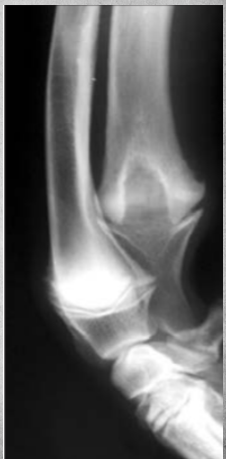

Describe Premature closure of growth plate.

A

e.g. distal ulna such as in image

results in growth discrepancy and may disrupt the function of the joint

What does this depict?

Premature closure of growth plate distal radius.